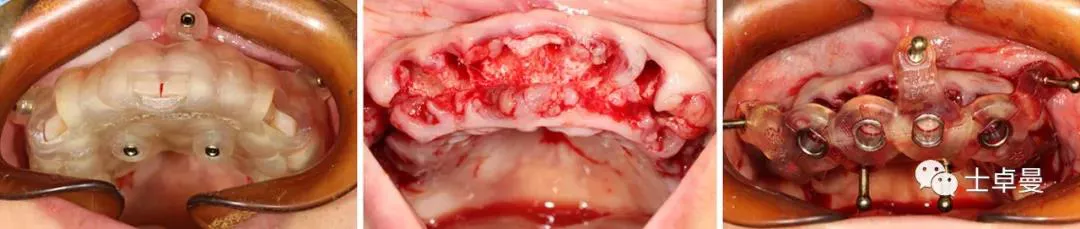

下颌种植手术

· 手术操作流程与上颌基本一致,最终植入4颗Straumann BLT种植体,植入扭矩均达到45Ncm以上:

✓ 35、45:4.1mm×14mm

✓ 32、42:3.3mm×12mm

· 安装SRA基台,均加力至35Ncm:

✓ 35、45:RC30°4mmA型

✓ 32、42:NC直型2.5mm

· 旋入SRA基台保护帽,修整粘膜,缝合。

· 手术完成后复查CBCT与术前设计对比,验证植入精度。

· 术后放弃固位钉引导修复体就位,改用传统的pick-up技术口内粘接术前制作的临时修复体;